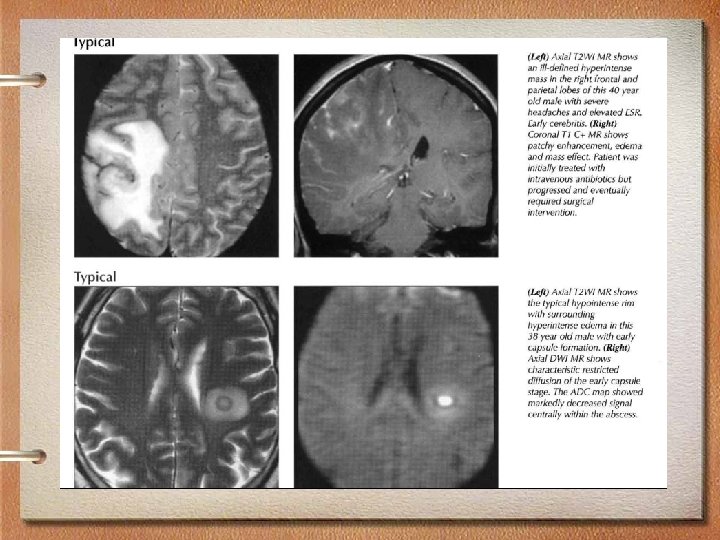

MRI findings • Imaging varies with stage of abscess development • Early capsule: Well-defined, thin-walled enhancing rim • Ring-enhancing lesion with high signal • T 2 hypointense abscess rim with surrounding edema • Typically supratentorial • Frontal and parietal lobes most common, gray-white junction (hematogenous)